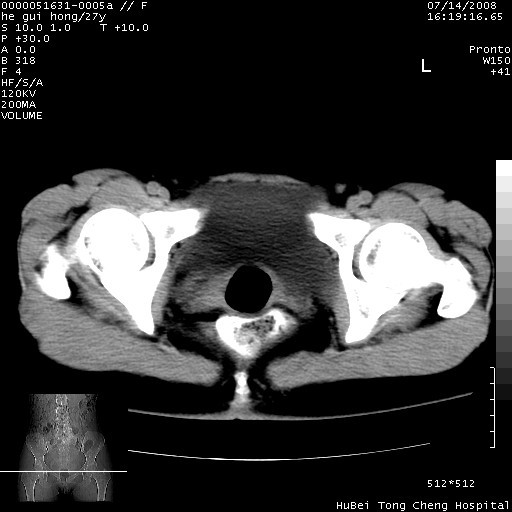

以下是引用杀毒软件在2008-7-20 8:03:00的发言:[br]支持双侧卵巢囊腺瘤可能性大!

以下是引用zjzjr在2008-7-20 13:36:00的发言:[br]双侧附件囊腺瘤可能性大!